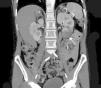

The extent of ischaemic injury was estimated in each patient by dividing the kidney into six segments, such that ARI of the renal poles, with no involvement of the rest of the kidney or the contralateral kidney, was considered to have 1/6 degree of damage (17%) (Figs. 1 and 2). Thus, the estimated injury extent for each patient could theoretically range from 1/6 (17%) to 6/6 (100%).

Estimated mean extent of ischaemic damage measured by CT scan was 35% (2/6 of the total renal parenchyma), with peripheral wedge-shaped hypoperfusion present in 70% of cases, global involvement in 21% of cases and multifocal involvement in 9% of cases. All patients had two native kidneys and there were no cases of previously reported renal atrophy. No differences were found between the subgroups in terms of predominant involvement of the left or right kidney (Table 1).

A contrast-enhanced CT scan reveals perfusion defects, sometimes accompanied by cortical rim sign, which correspond to the blood flow through collateral arteries19 (Fig. 2). If, intravenous contrast is not used, ARI may not be recognised.20